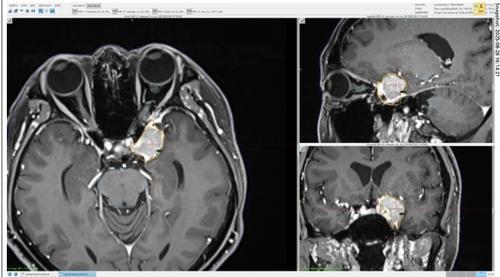

■病例2

吴太太现年54岁,4年前我第一次见她,当时她的颅颈交界处长了一颗约三四公分大的脑膜瘤,压迫主要神经中枢,导致她四肢无力,整天病恹恹的,觉得浑身不对劲。

肿瘤的位置在喉咙后方,手术切除后还有10%残留,无法完全根除,但吴太太的行动力已恢复,可以如常生活,每年的追踪报告也无异样。另外,我当时也发现她左眼后方有一颗体积约1公分的脑膜瘤,由于没有影响视觉,所以只作保守治疗,每年追踪观察。

到了近两年,这颗小肿瘤开始有逐年增大的迹象,但吴太太的视觉暂时还正常,没有看到黑影,也没有复视。虽然如此,吴太太仍然惴惴不安,觉得头颅内好像潜伏着一枚定时炸弹,不晓得何时会突然爆发。

她想要切除肿瘤,但又极之不愿意再挨刀子,于是就选择了伽玛刀。

一次性无刀清除两肿瘤

我决定用伽玛刀一次性处理吴太太的两颗肿瘤,即左眼后方的脑膜瘤,以及颅颈交界处、外科手术后残留的脑膜瘤。

由于肿瘤的体积不大,单次疗程就已足够,放射剂量为14Gy。治疗时,吴太太必须戴上头架,头架通过4个销钉连接到头骨,以便精确定位和稳定头部,接着,吴太太就躺在治疗床上,进入伽玛刀仪器中,在那里,头架会和仪器内的头盔牢牢固定在一起,放射线则从192个方向精确地照射到病灶上。